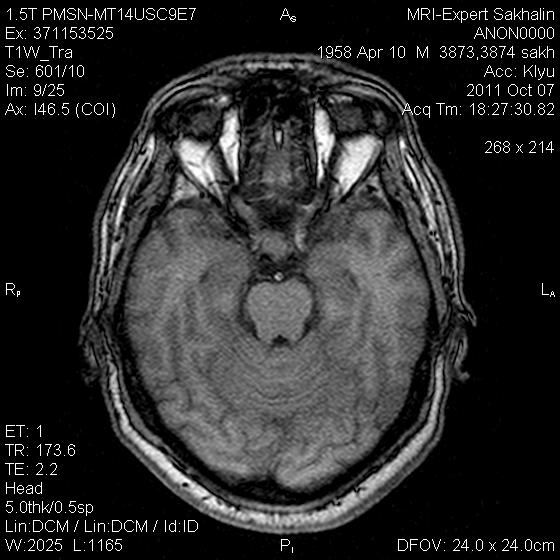

Аденома гипофиза

Вот такая аденома гипофиза сегодня.Мужчина с жалобами на снижение зрения.

постконтраст